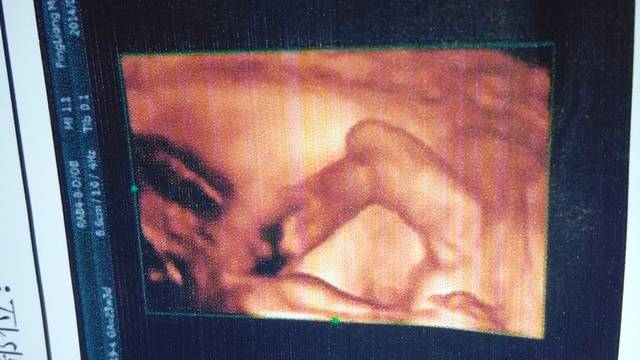

请帮忙看一下是男孩女孩 请帮忙看一下是男孩女孩 点击展开 蓝海、伊沫 2014-09-13 15:16 为您推荐: 其他回答 呵呵 。。。 莉莉(≥3≤) 2014-09-13 15:39 是不是看见掉把子了呀 莉莉(≥3≤) 2014-09-13 15:36 我看好像是宝宝的脚 @愿得 一人心 2014-09-13 15:24 这是哪?。。 @愿得 一人心 2014-09-13 15:19 B超单子上是不允许有有性别的信息透露的的,只有医生当时做的时候才能看到的一般不会说的。 panshanneng 2014-09-13 15:17 相关问题 帮忙看一下是男孩女孩,谢谢,男孩女孩都是宝,只是好奇 请帮忙看一下怀孕数据3 0*207*1 9能看男孩女孩吗 娱乐一下,宝妈们看一下男孩女孩~